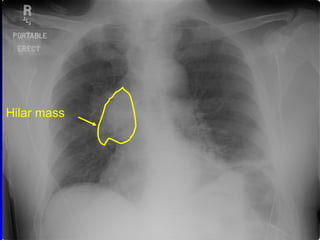

Chest mass, emphysema Hilar mass